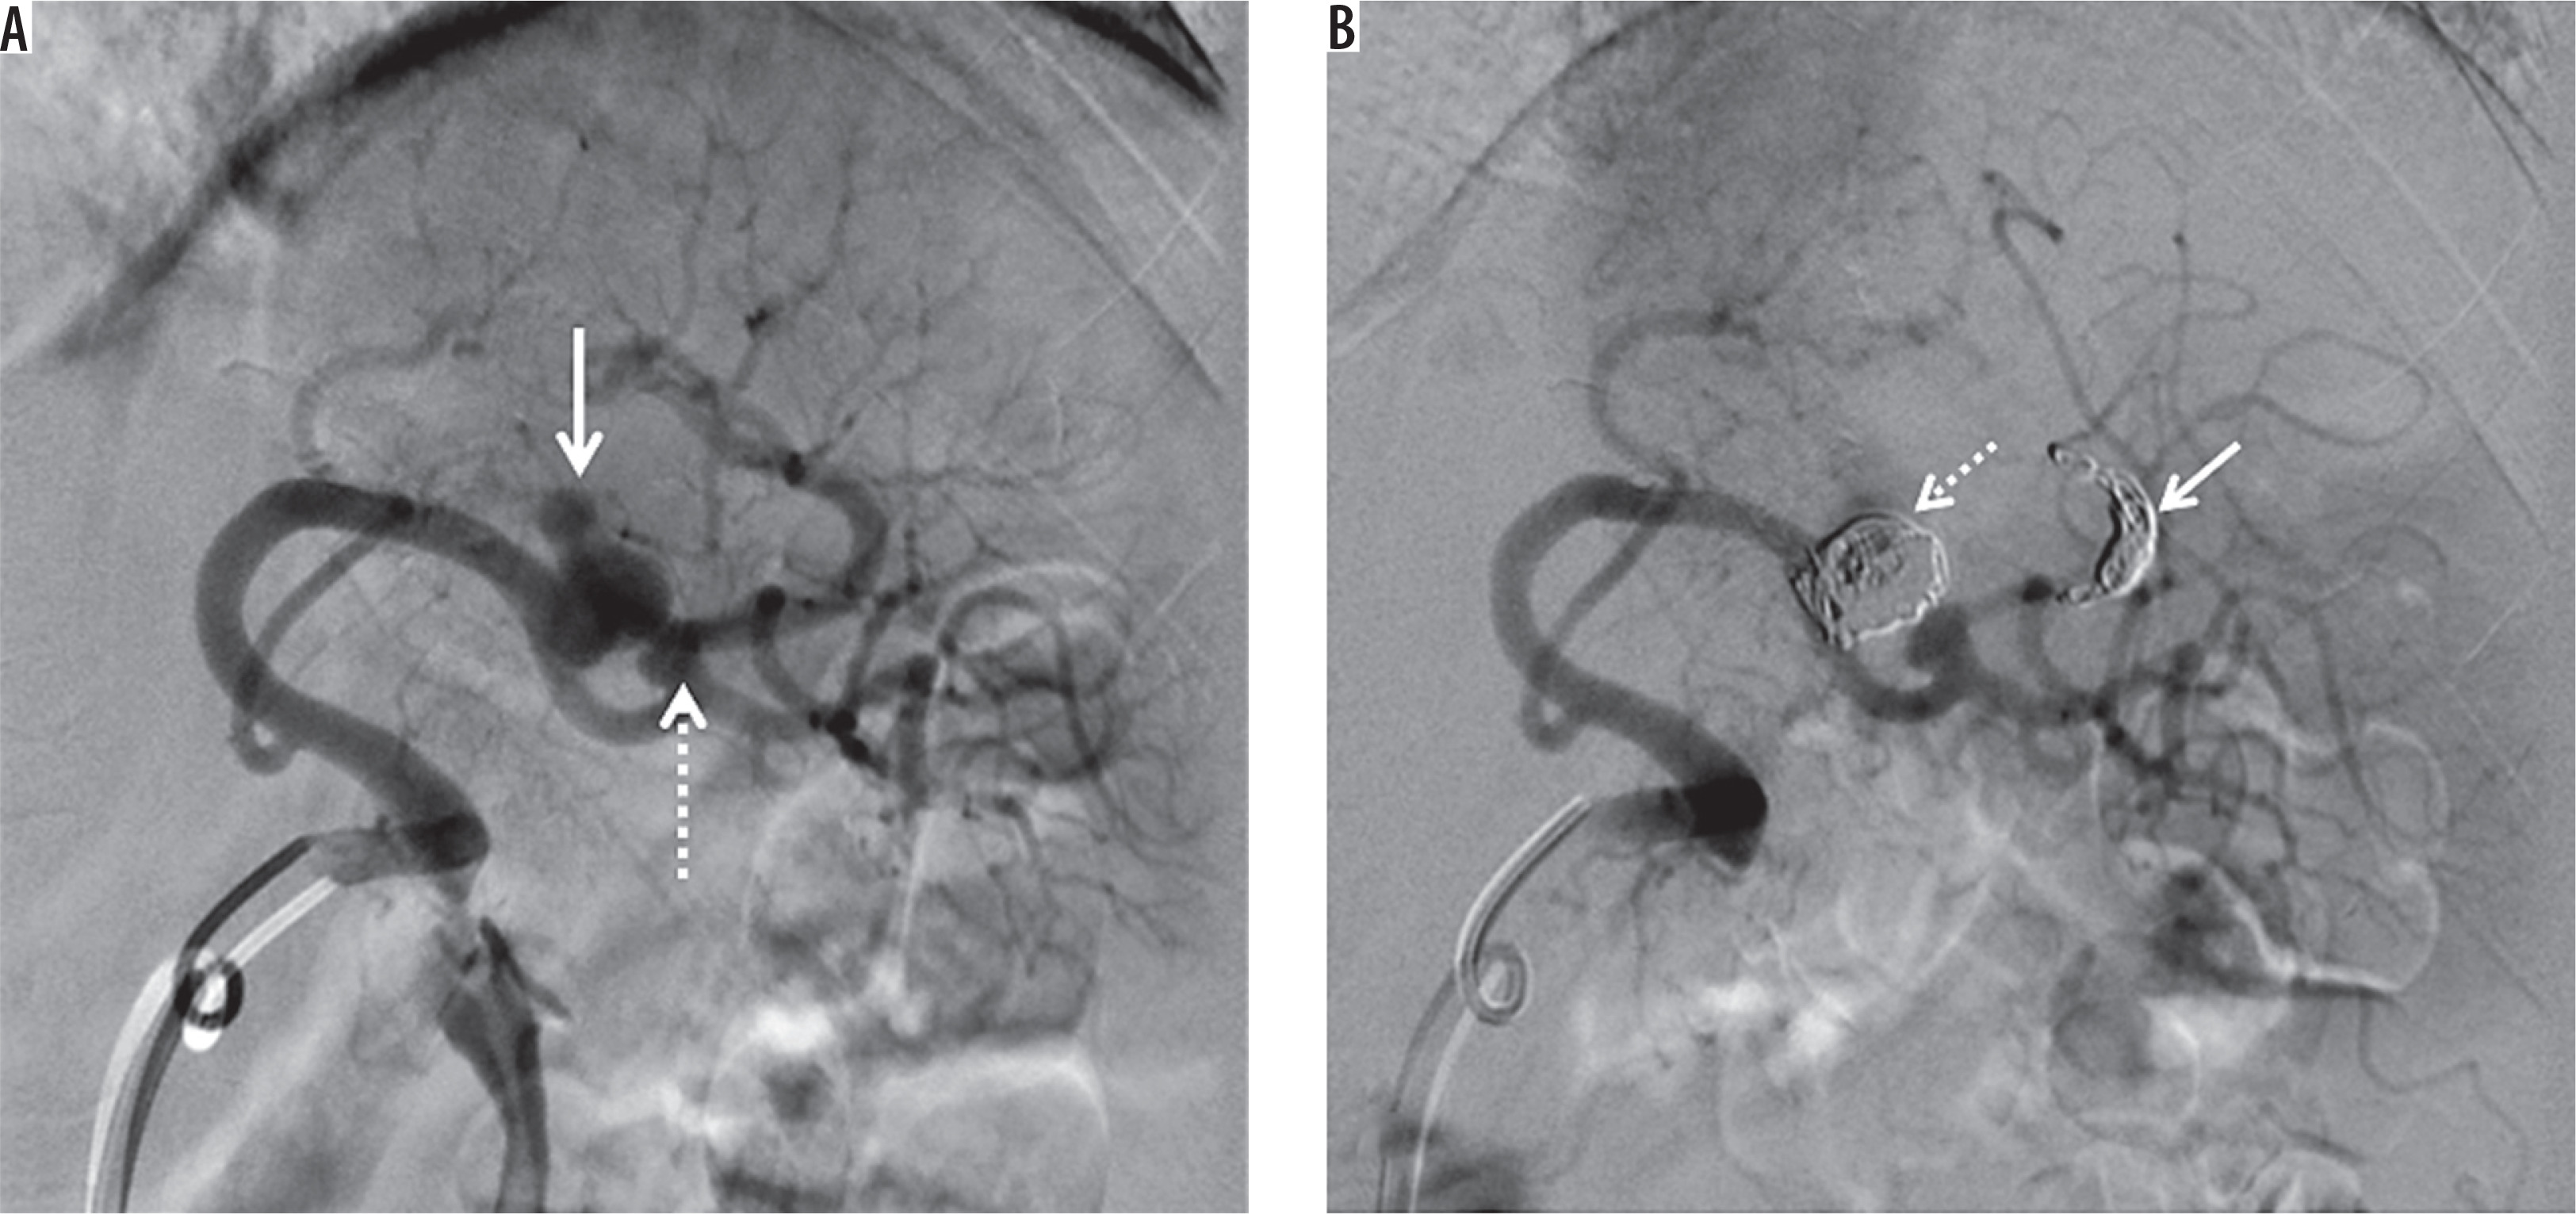

Figure 7

Splenic artery pseudoaneurysm caused by blunt abdominal trauma. A) Splenic arteriogram obtained before intervention shows two pseudoaneurysms (arrow and dotted arrow). B) Digital subtraction angiography demonstrates exclusion of the big pseudoaneurysm by distal coil embolization (arrow) and embolization of the pseudoaneurysm itself (dotted arrow). We decided to follow up the small pseudoaneurysm to protect the splenic blood flow